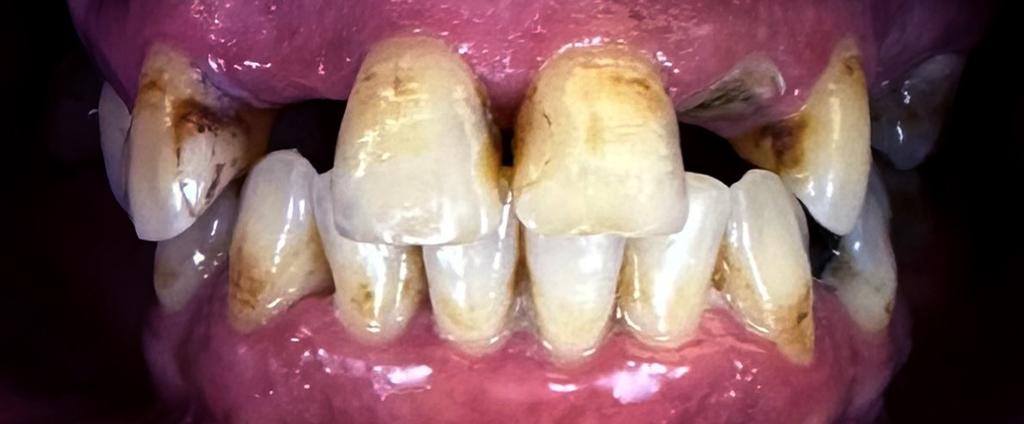

1. Konsultacja z ekspertem

Podczas pierwszej wizyty lekarz implantolog wykonuje badanie wewnątrzustne, tomografię komputerową (CBCT) podczas której, weryfikuje ilość oraz jakość kości wyrostka zębodołowego. Jeśli z powodu znacznej atrofii wykonanie metody All-on-6 okaże się niemożliwe zaproponujemy inne rozwiązanie. Konsultacja taka kończy się wykonaniem planu leczenia wraz z kosztorysem.

Na tym etapie rozpoczynamy proces planowania leczenia. Spotkasz się z lekarzem implantologiem oraz zostanie przeprowadzona pełna higienizacja Twoich zębów. Ponad to, pobierzemy cyfrowy wycisk jamy ustnej, wykonamy niezbędne fotografie oraz wykonamy pełną diagnostykę w celu przygotowania szablonów chirurgicznych i prac tymczasowych.